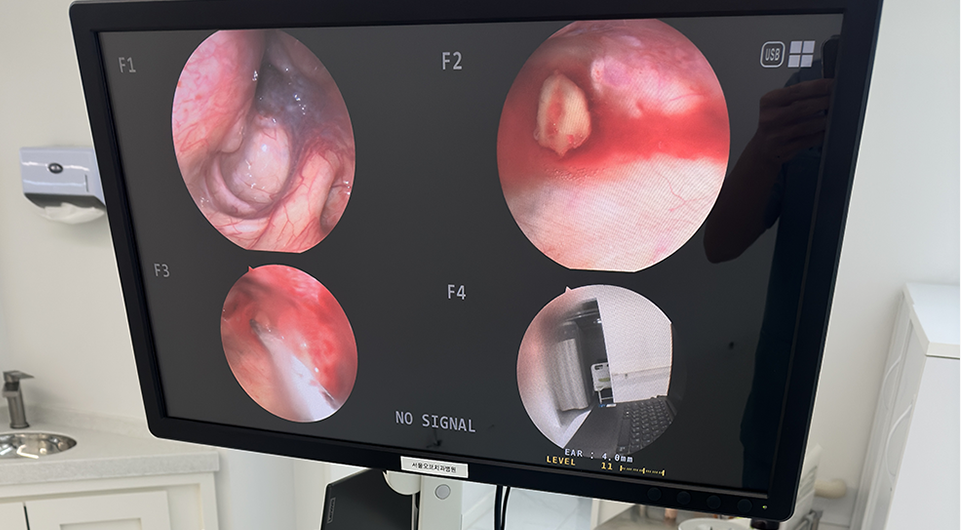

서울오브치과병원은

인체에 유해한 금속 성분을 사용하지 않으며,

환자의 구강 상태와 치료 목적을 면밀히 고려해

장기적으로 안전하고 기능적인 보철물만을 선택합니다.